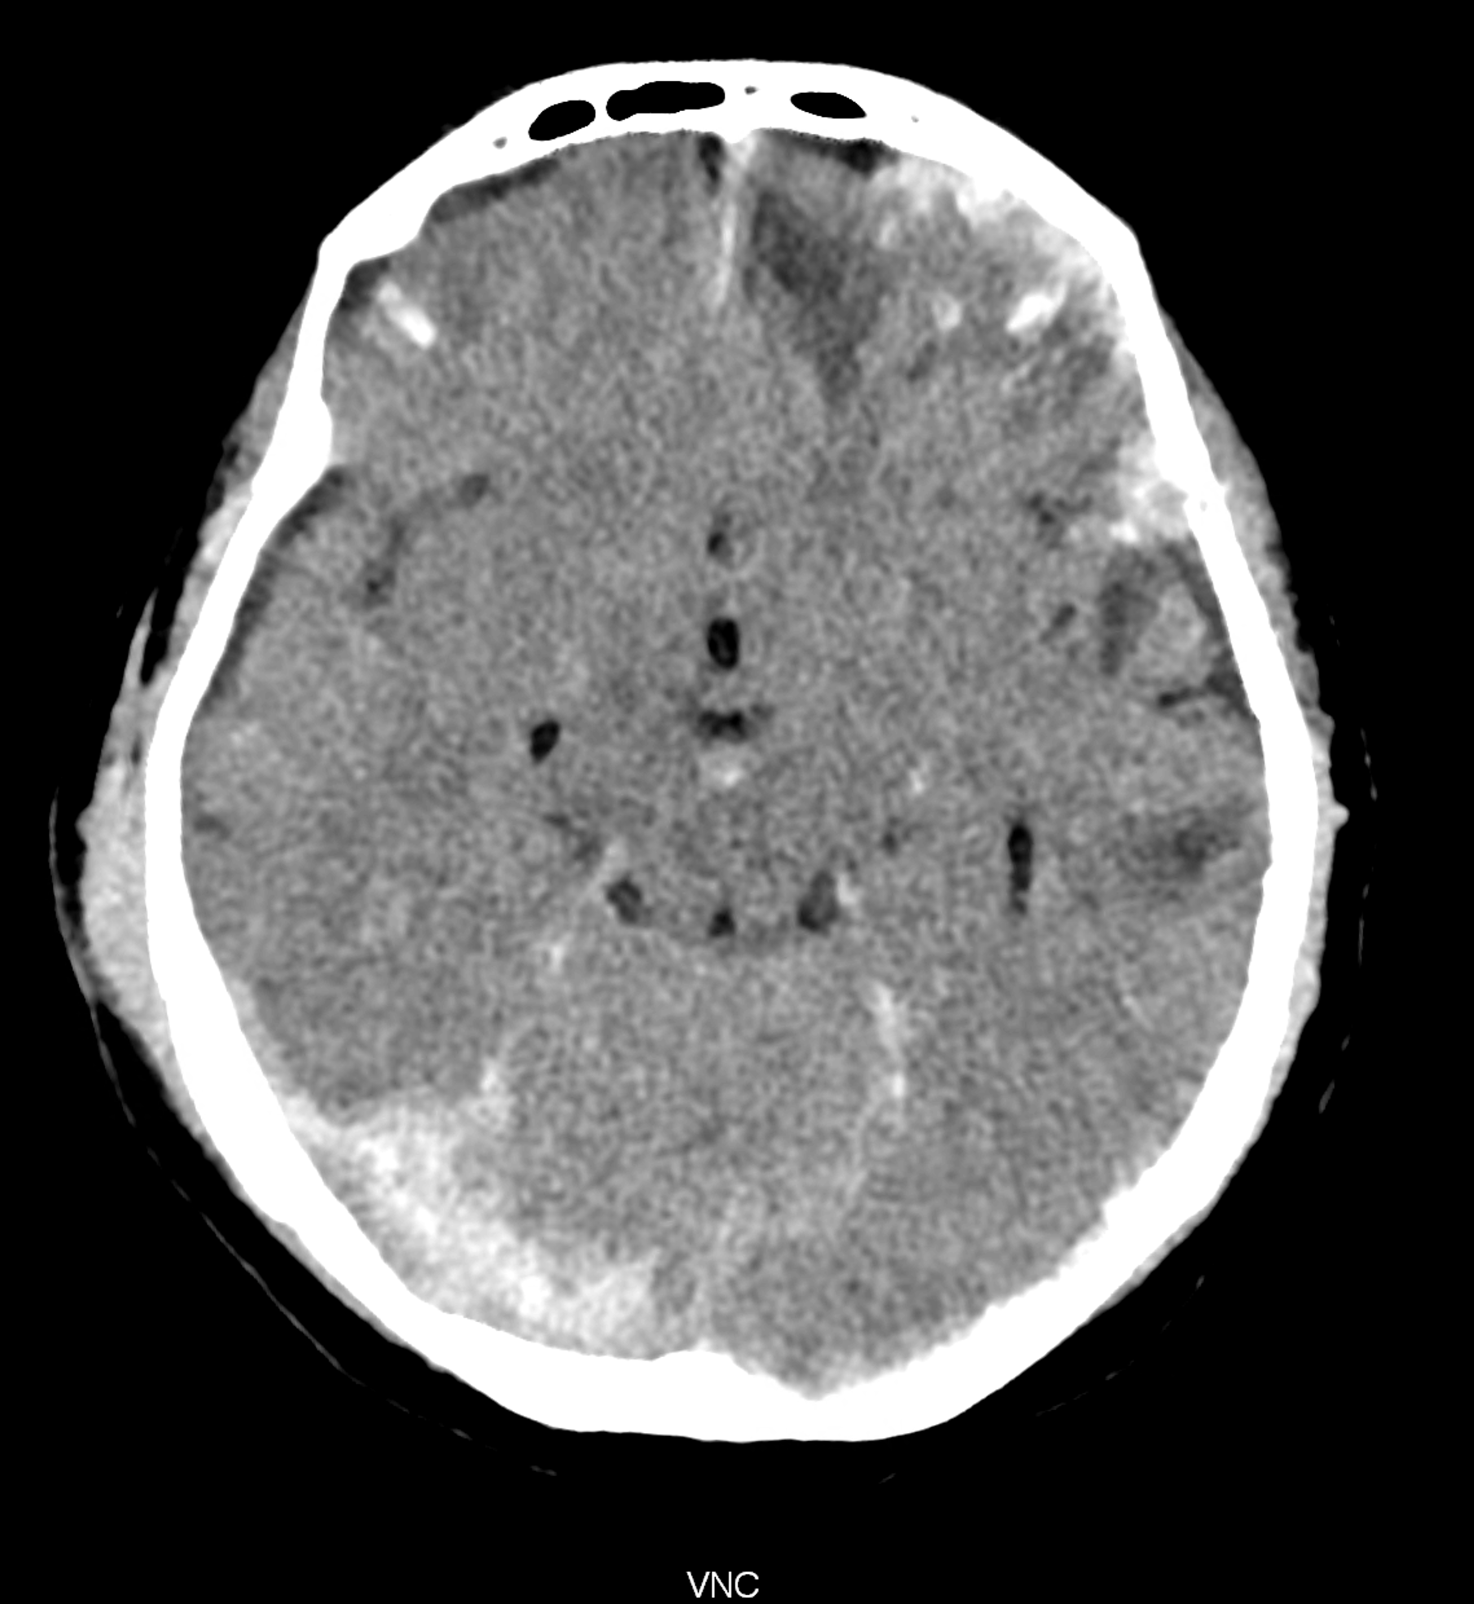

Bleeding is characterized by different absorption characteristics than healthy brain tissue (both gray and white matter) and cerebrospinal fluid. Due to the higher proportion of proteins with amino acids with disulfide bonds, the signal intensity increases at higher energies, making it possible to use monoenergetic imaging at energies above 140 keV, and/or virtual non-contrast. The hemorrhage then becomes more hyperdense, while the rest of the brain tissue acquires a uniform low signal. In addition to bleeding, areas of extracellular fluid of vasogenic origin are also imaged, i.e., in areas around contusion-type brain tissue injuries.

An example of the use of spectral imaging in complex brain injury, where contusions, diffuse axonal injury, subarachnoid hemorrhage, subdural hemorrhage, and blood in the ventricular system are present.

comparison of the images with the energies of monoenergetic reconstructions 40 keV, 67 keV (standard conventional reconstruction), 190 keV and virtual non contrast (VNC)